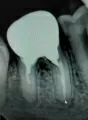

Мне поставили коронку на место. Но как только я перестала колоть антибиотик, боль под коронкой опять стала беспокоить, особенно во время еды. Появилась реакция на любую температуру — прохладное или тёплое (холодное и горячее). На снимке каналы запломбированы хорошо.

Не достаточно информации для грамотного ответа на интересующий Вас вопрос.

Дополните его рентгеновскими снимками, и советую сделать Вам компьютерную томограмму для уточнения диагноза.